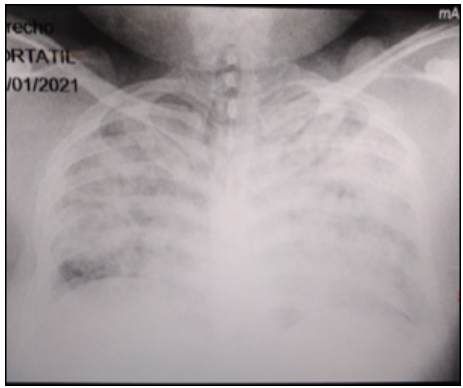

Varón de 34 años con antecedente de hipertensión arterial en tratamiento con losartán, ingresó con un tiempo de enfermedad de 6 días, con tos seca, fiebre de 38,5°C, dolor faríngeo, medicado en casa con paracetamol, ceftriaxona y dexametasona, sin mejoría. Un día antes del ingreso presentó disnea que progresó rápidamente hasta disnea en reposo, por lo que acudió al Hospital Cayetano Heredia. En el examen clínico al ingreso se encontró PA: 120/70 mm Hg, FC: 95 x min, FR: 28 x min, Sat02 : 96% con mascara de reservorio a 15 litros/min, peso: 130 kg, talla: 1,75 m, IMC: 42 kg/m2, regular estado general, tirajes, aleteo nasal, crepitantes basales bilateral, respiración toraco-abdominal, Glasgow 15. La radiografía de tórax mostro infiltrado alveolar bilateral, hemograma con leucocitos 10 000/mm3, linfocitos 870/mm3, plaquetas 320 000/mm3, hemoglobina 13,9 g/dl, proteína C reactiva 96 mg/dl, dímero D 0,4 mg/l, urea 25 mg/ dl, creatinina 0,9 mg/dl, sodio 144 mEq/l, potasio 4,18 mEq/l, DHL 635 UI/l; lactato 2,1 mmol/l, Pa02/ Fi02 186 y PCR – RT para SARS - CoV2 positivo. En el examen de orina al día 11 de hospitalización, se encontró hemoglobina y proteínas positivo, pH 5 y sedimento con leucocituria mayor de 100 x campo, leucocitos aglutinados 2+ y hematuria 30-40 x campo; el urocultivo fue negativo.